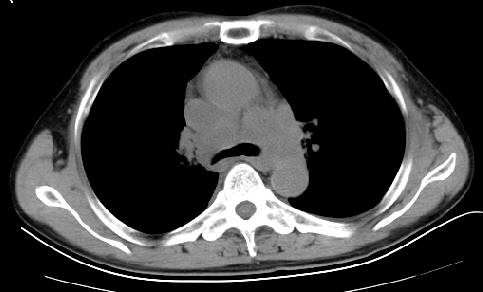

以下是引用草之原在2009-5-2 19:29:00的发言:[br]1.考虑右侧中心型肺ca纵膈淋巴结转移,双侧胸腔积液及右侧叶间裂积液,心包积液。[br]2.两肺上叶病灶,纵膈窗显示部分病灶硬化,考虑:结核。[br][br] [br]

以下是引用ct诊断高手在2009-5-2 19:08:00的发言:[br]我考虑右侧中央型肺癌 伴右肺节段性不张,两肺及纵隔淋巴结转移,右侧胸腔积液。

以下是引用zjzjr在2009-5-2 20:16:00的发言:[br]肺结核,转移瘤.纵隔淋巴结转移或淋巴瘤,右侧包裹性积液、斜裂积液。心包积液。